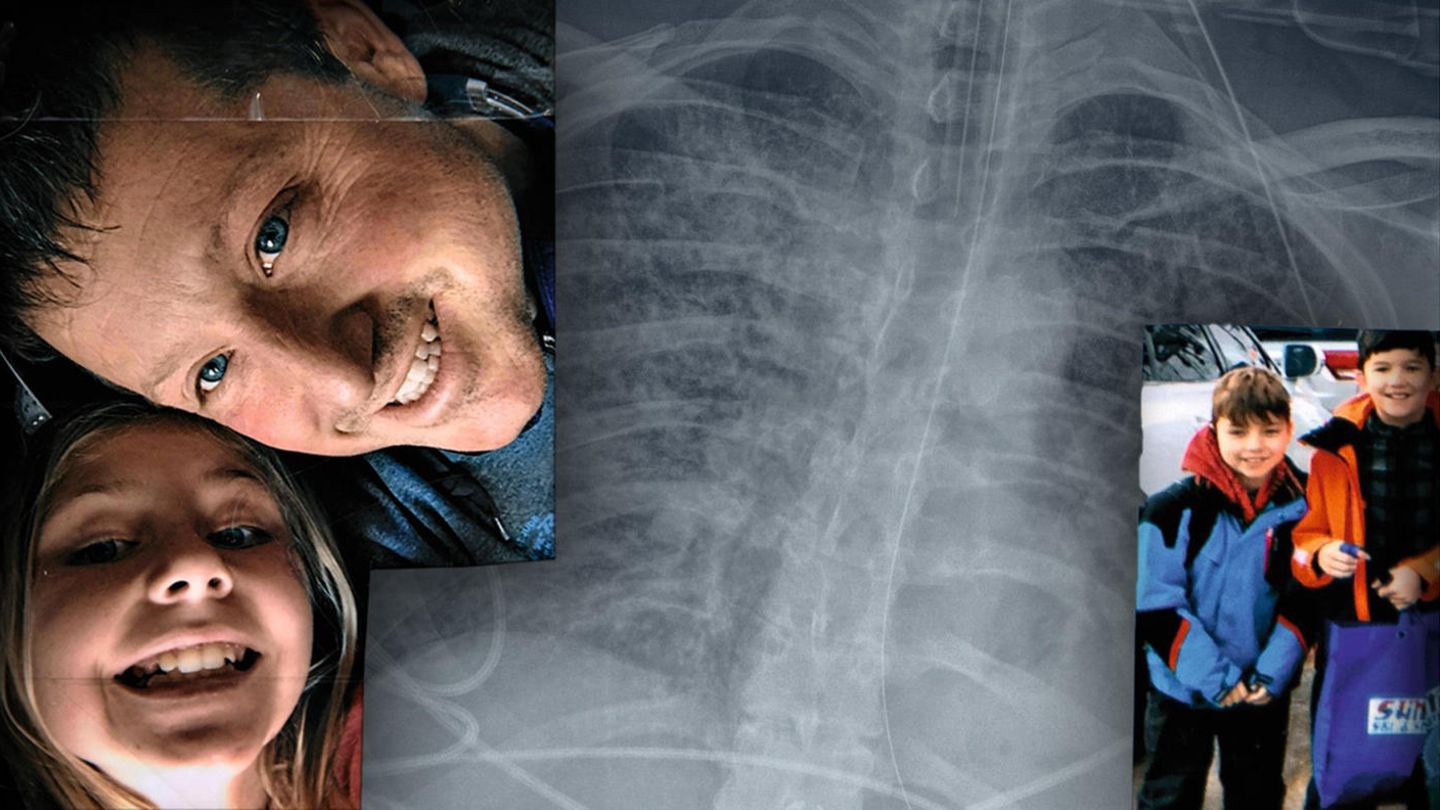

Ein Familienfoto zeigt Jim Bello mit seiner Tochter Hadley, 13. Rechts die Zwillinge Taylor und Riley, 11

Schwerer Krankheitsverlauf Ein Familienvater erkrankt schwer an Covid-19. Für 32 Tage hängt er an der Beatmungsmaschine – und überlebt

Jim Bello, 49 Jahre und gesund, erkrankt schwer an Covid-19. Kein Medikament will anschlagen, nur das Beatmungsgerät hält ihn am Leben. Es bleibt nur eine Hoffnung: Sein Blut außerhalb des Körpers mit Sauerstoff anreichern.